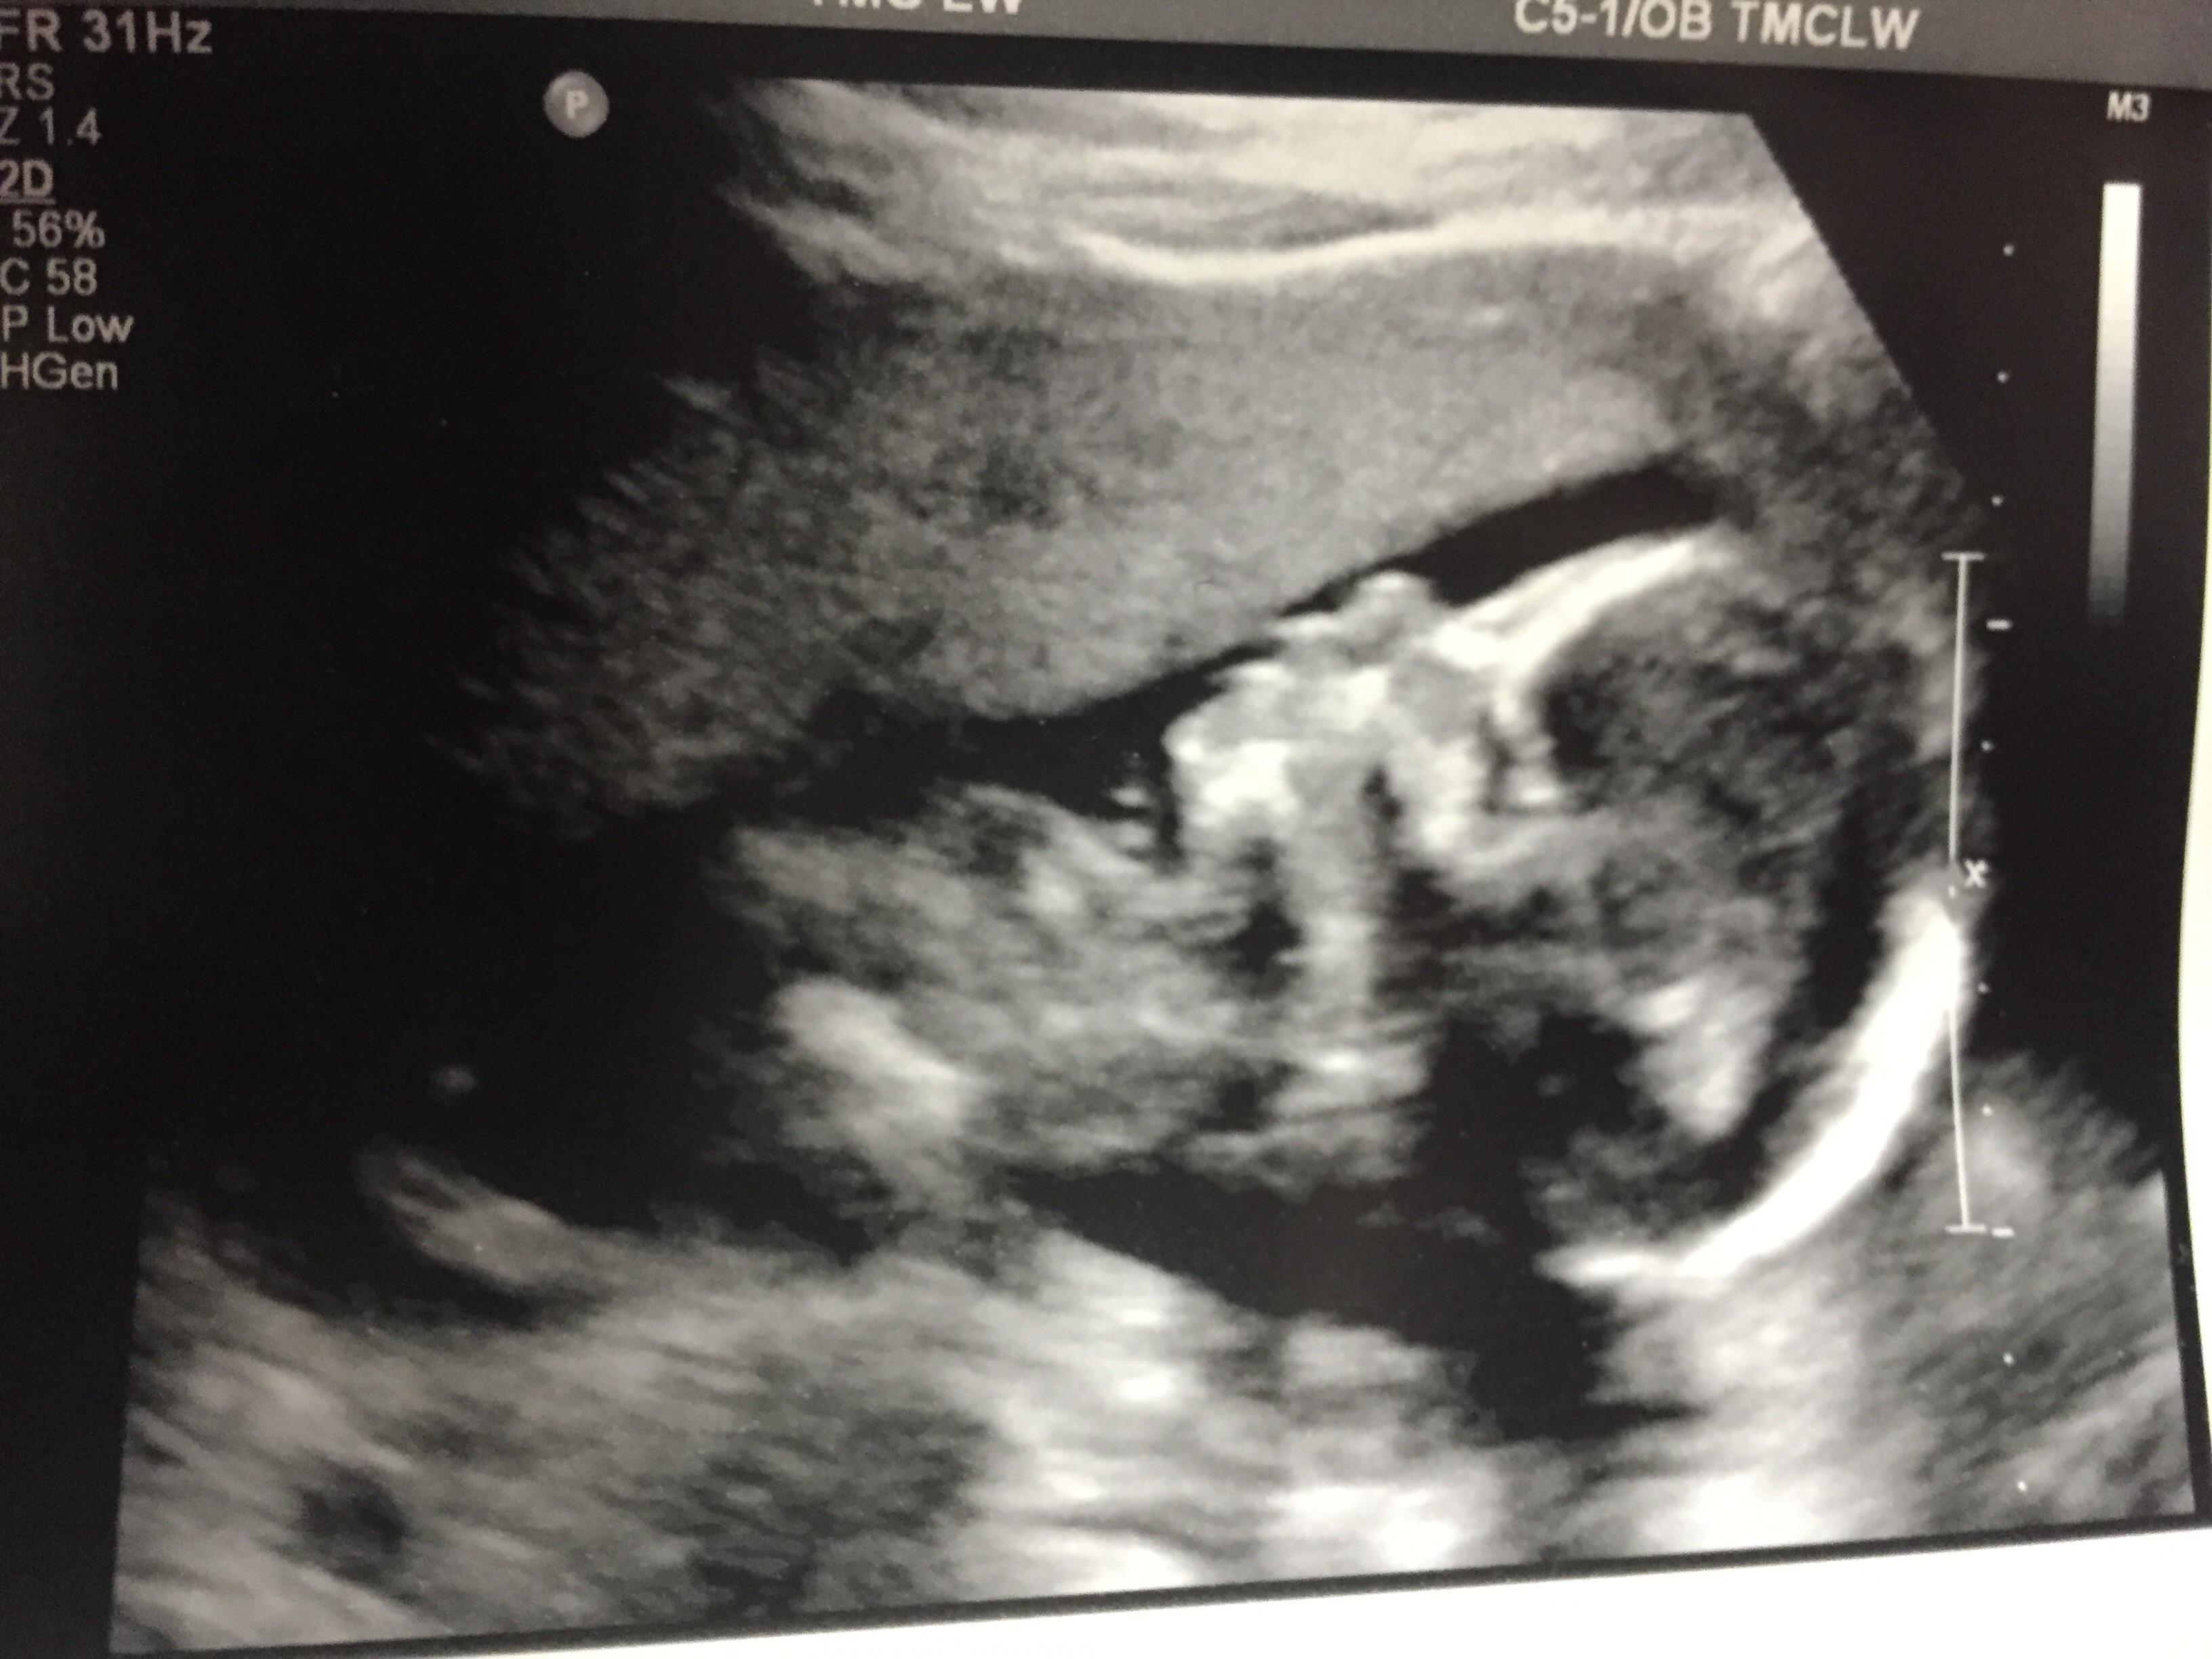

...and it's a girl!! Holly Blake is due October 12th

image.jpg